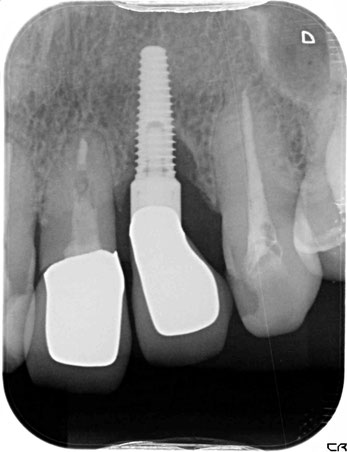

初診時のレントゲン写真。インプラントの周囲の骨がなくなってしまっています。